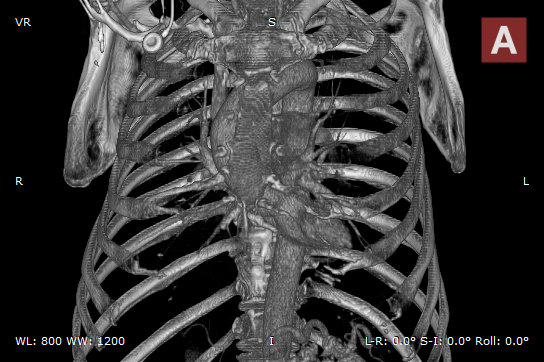

Bones and skin 1

Bones and skin 2

Bones and skin 3

Bones B/W